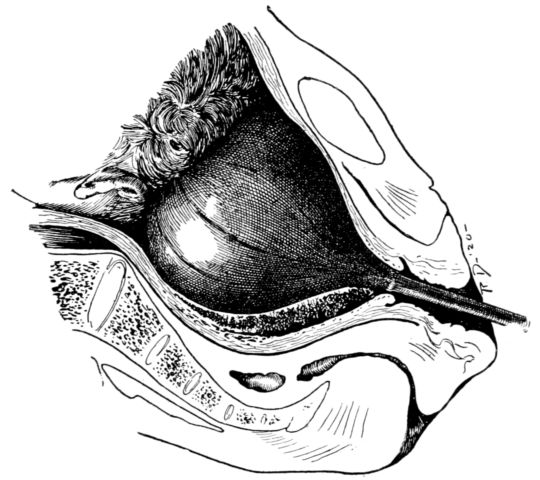

| 47. | Champetier de Ribes’ bag inserted in uterus | 177 |

| 112. | Champetier de Ribes’ bag | 311 |

| 113. | Voorhees’ bag | 312 |

| 114. | Bag held in forceps for introduction into uterus | 312 |

| 115. | Syringe for filling above bags after insertion | 312 |